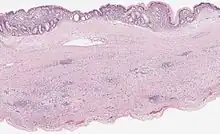

| Mucinous cystadenoma of the pancreas 6 |

- Pancreatic mucinous cystadenoma